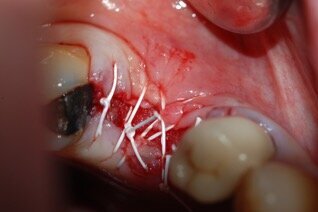

I lembi sono stati poi suturati a livello dell’osso (Gore-Tex®, 4.0, Gore, Newark/ NJ, USA) senza la necessità di ottenere una chiusura completa (Fig. 3). In fase postoperatoria è stato prescritto un antinfiammatorio (Nimesulide 100 mg, 2 volte al giorno per 3 giorni), un analgesico (Paracetamolo 500 mg, 1 compressa ogni 8 ore per 3 giorni) e clorexidina 0.12%, e fornita istruzione completa all’igiene orale. La sutura è stata rimossa dopo 10 giorni. A 3 e a 6 mesi sono state eseguite le radiografie periapicali parallele.